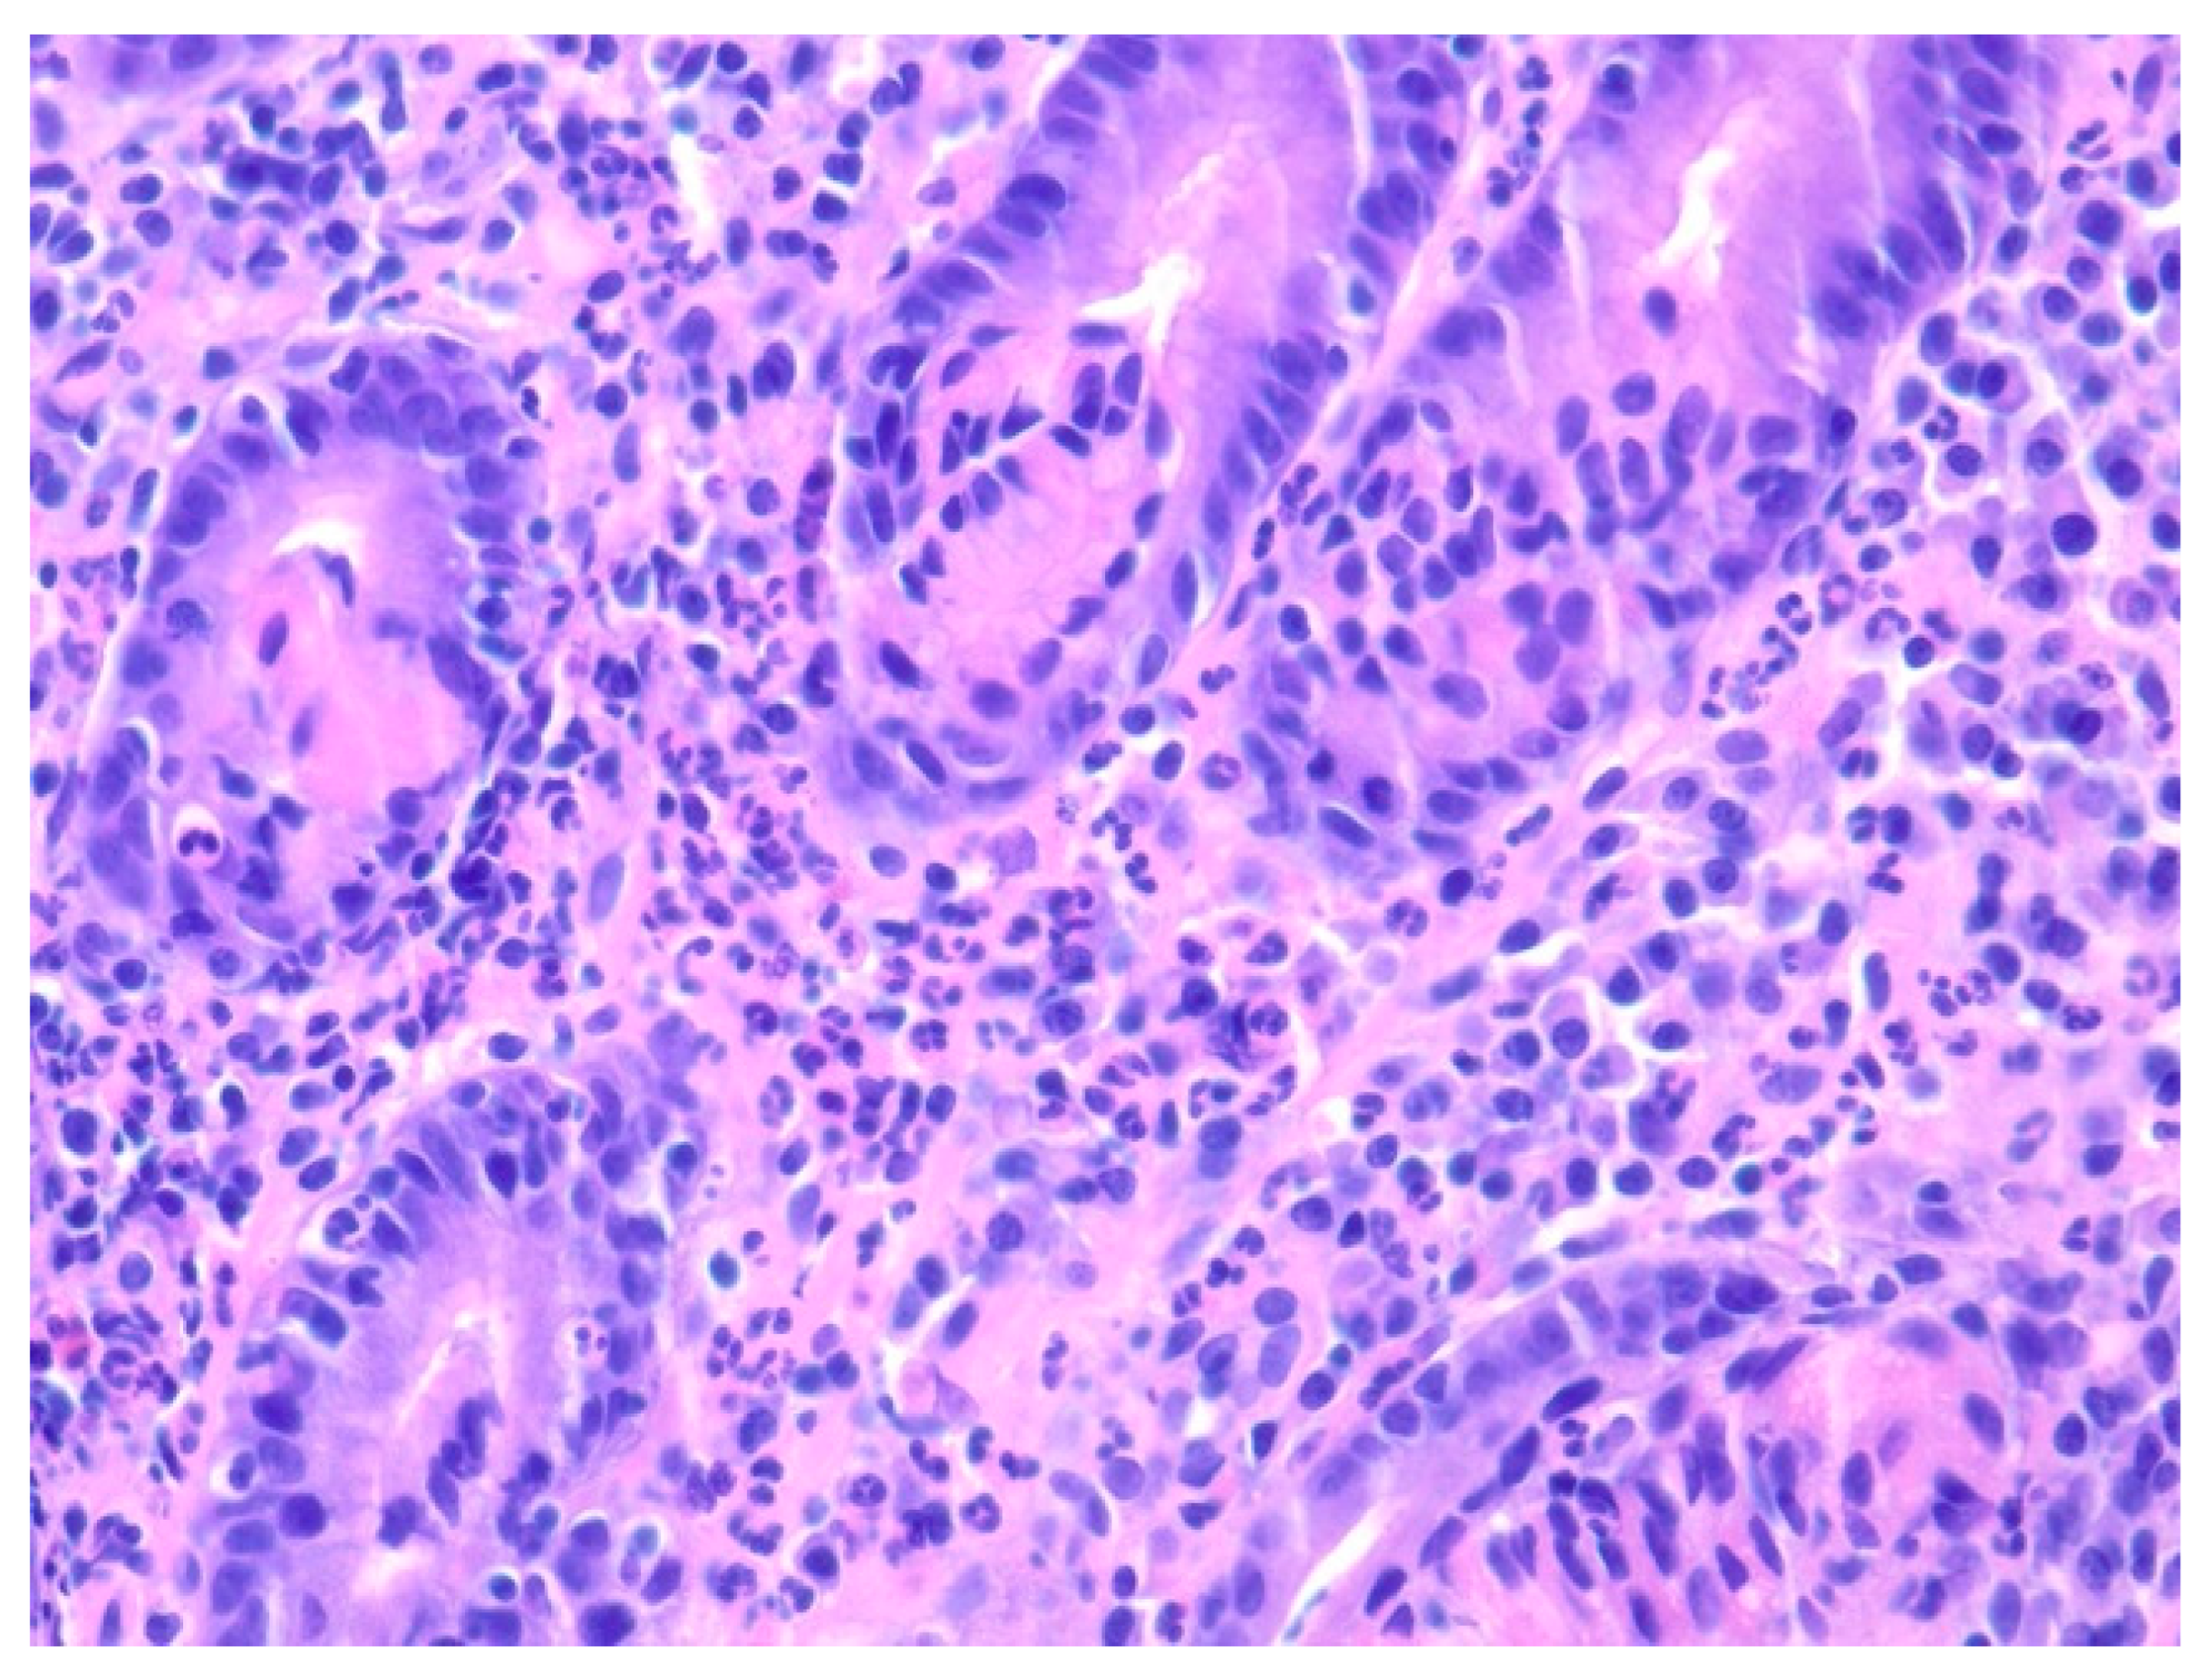

| 3 | F | 35 | Lung | Fundus | Fungating mass | Esophagus, mediastinum | Large-cell neuroendocrine carcinoma | Chemotherapy-carboplatin/ etoposide | Death 1 month after EGD diagnosis of metastasis |

| 4 | F | 73 | Kidney | Fundus and body | Multiple large friable masses | Liver and lungs | Clear cell renal carcinoma | Nephrectomy, chemotherapy, immunotherapy (Axitinib) | Death 10 days after EGD diagnosis of metastasis |

| 5 | M | 76 | Lung | Body | Cratered ulcers | Liver, bone and adrenals | Small cell carcinoma (poorly differentiated neuroendocrine Ca) | None | Death 7 days after EGD diagnosis of metastasis |